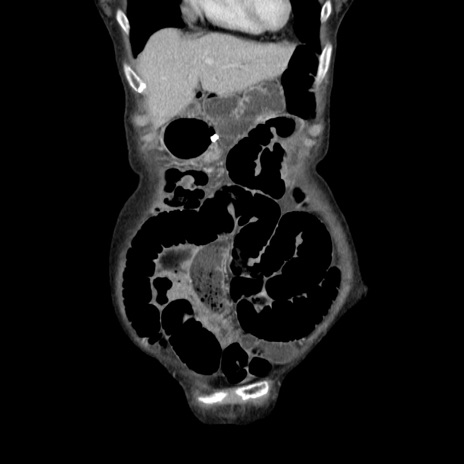

症例25(冠状断像)

横断像